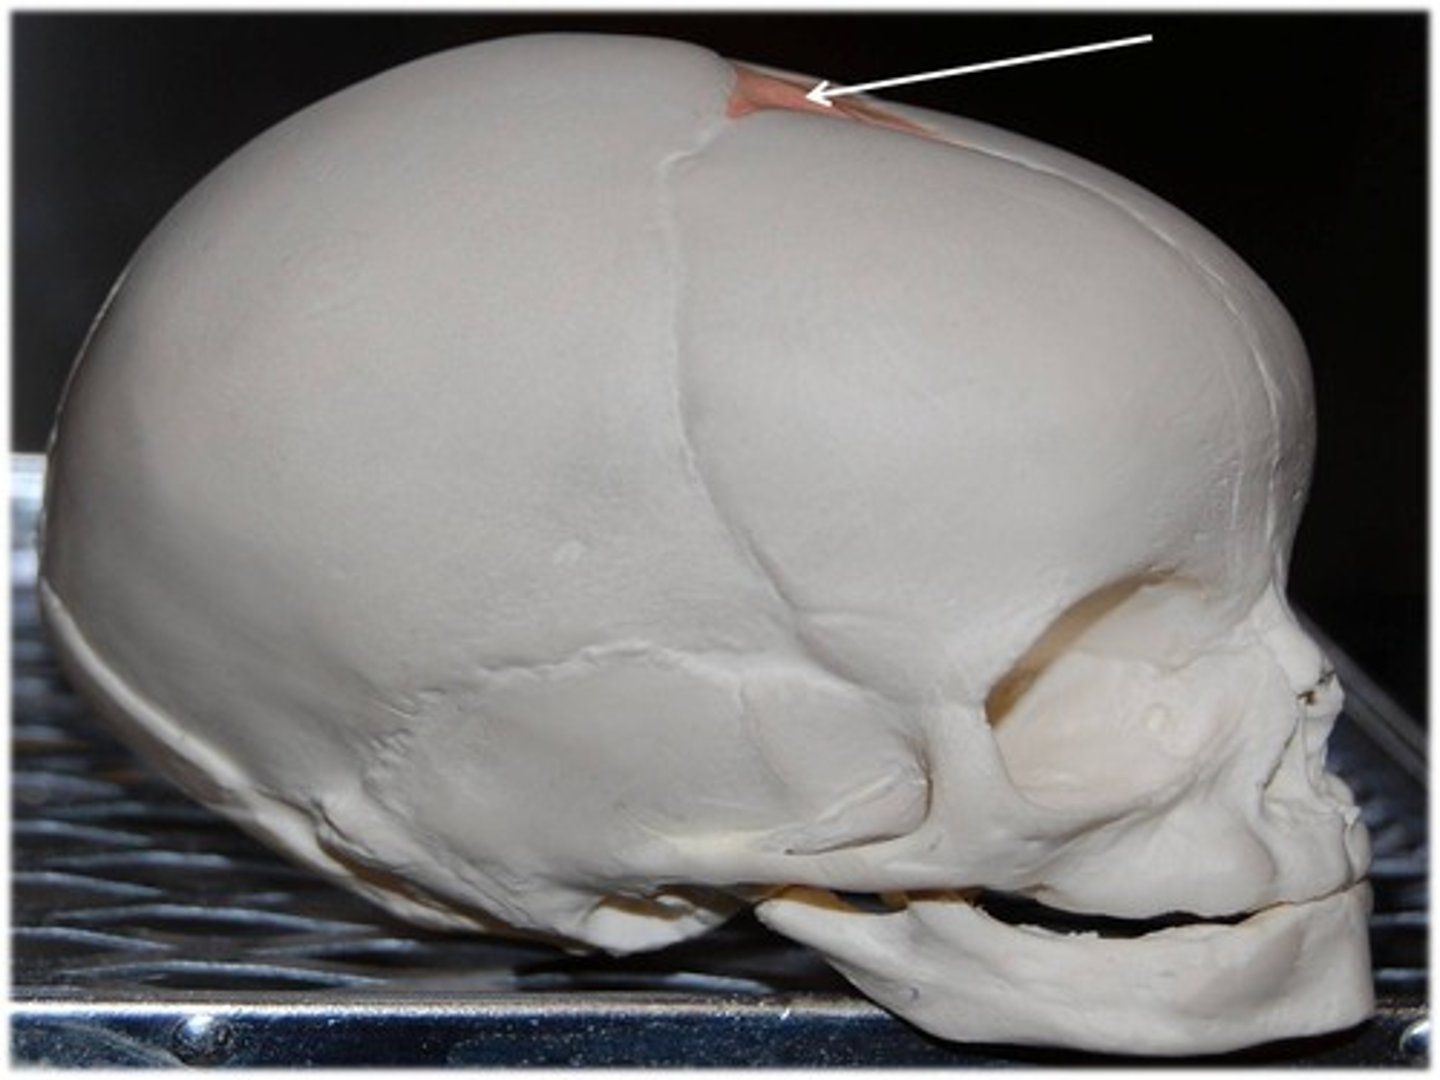

bregma

pterion